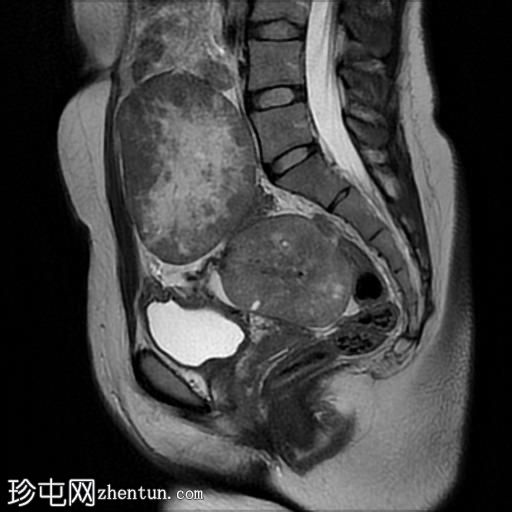

矢状位

T2加权像

1.jpg

盆腔内可见多个边界清晰的肿块:

其中一个位于子宫上方,T2加权像呈中等信号,中心区域呈高信号,增强T1脂肪抑制像未见强化。右侧卵巢增大,增厚的血管蒂扭曲,未见强化,轴位和矢状位T2加权像均显示清晰。

另一个位于子宫后窝,T2加权像呈中等信号,增强扫描显示明显强化。

轻度腹腔积液

2个月前进行的MRI检查显示双侧卵巢肿块均有强化,右侧卵巢肿块未见扭转。